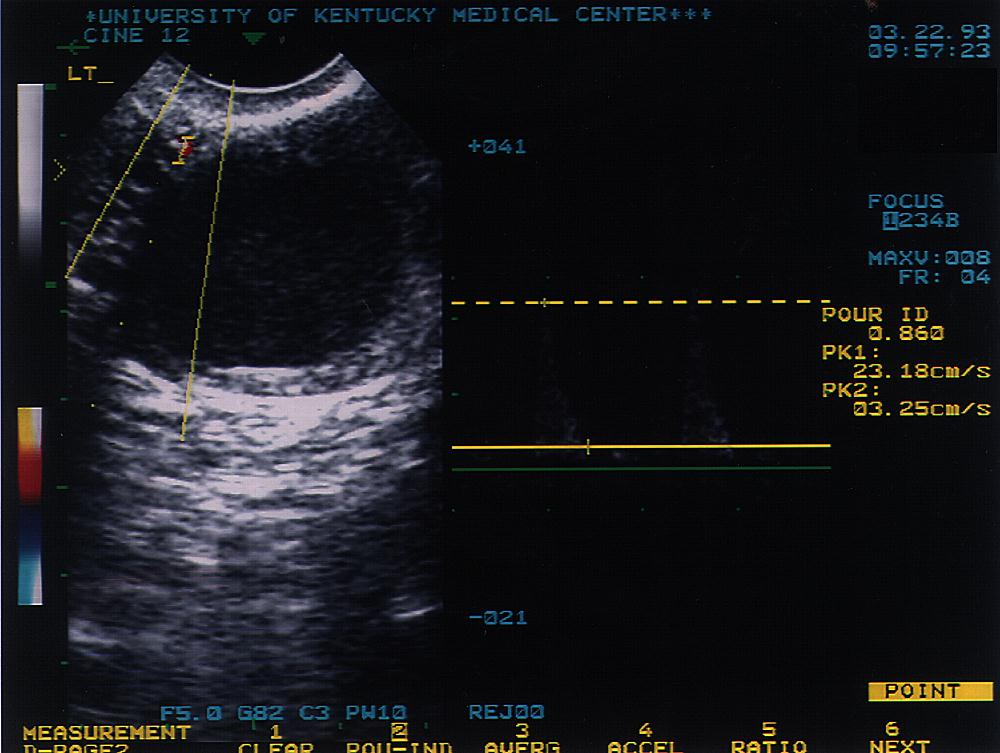

36 |

32.1 |

+ |

5 |

IA |

Mar-93 |